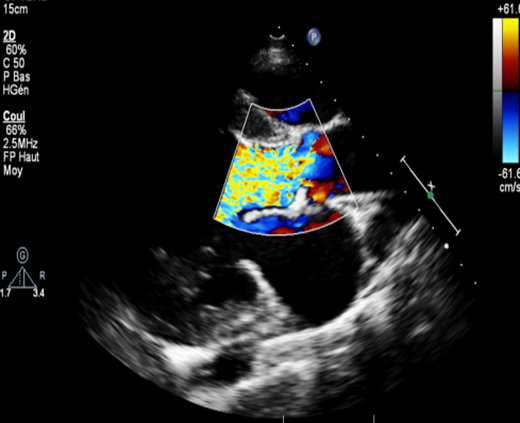

The ETT objectified a bicuspid aortic valve type 0, with severe aortic leakage: vena contracta at 8 mm, an ORS at 50 mm2 and a regurgitating volume (RV) at 80 ml; a dilated left ventricle with a telediastolic diameter at 64 mm and an LVEF at 60%; a left atrium dilated at 25 cm². The ascending aorta is undilated measured at 30 mm (Figures 3 and 4).

Figure 3: Parasternal long-axis view with color Doppler showing severe aortic regurgitation.

Figure 4: Parasternal short-axis view showing a type 0 bicuspid aortic valve, open during systole.